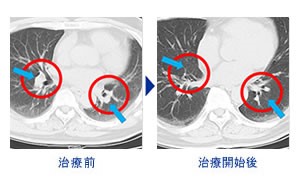

HANIL BIOTECH有限公司_治疗案例

乳腺癌 股转移(64岁女性)-照片-

乳腺癌・股转移(64岁女性)

癌症免疫疗法(NK细胞注射)NK・T细胞疗法+PD-1免疫抗癌剂

(抗PD-1抗癌剂)进行治疗。

1疗程5回、治疗中左乳腺癌症消失、骨转移癌症细胞消失。

治疗前摄影CT

治疗开始后的摄影CT

治疗前摄影CT

治疗开始后的摄影CT